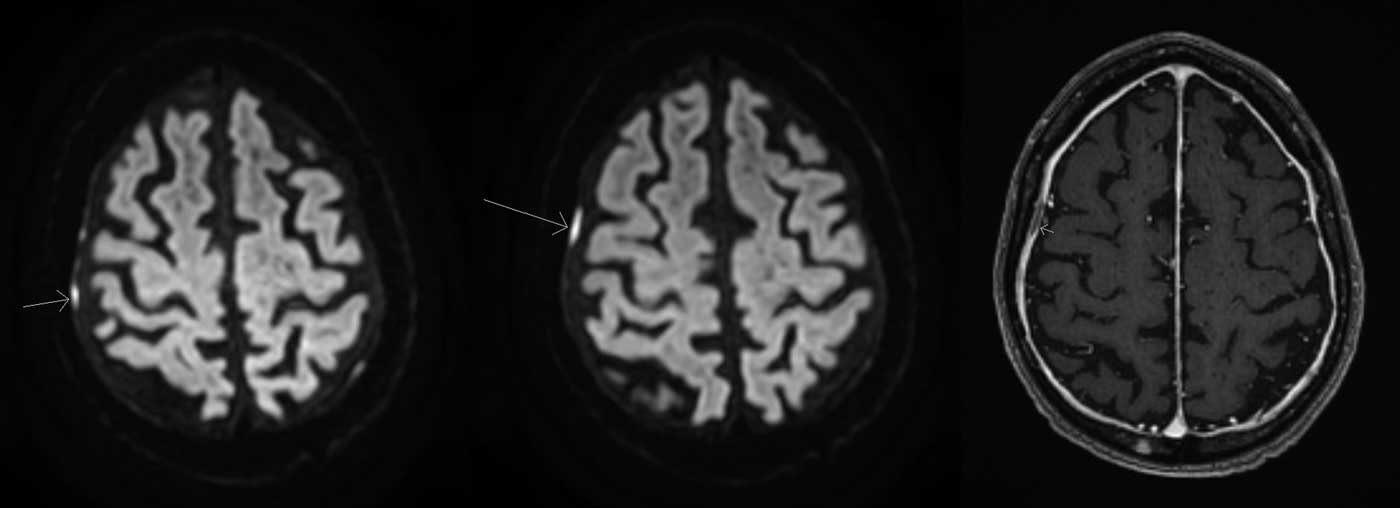

As part of the cardiac workup, an exercise thallium test was performed, whereby the patient exercised for 4 minutes 10 seconds, and demonstrated 2 mm upsloping ST depression infero-laterally with exertional angina. Myocardial perfusion imaging revealed a moderate volume of ischemia in the right coronary artery (RCA) territory. Coronary angiography (Figure 1) revealed a 90% distal posterior circulation stenosis that was felt to be too small for stenting, and non-flow limiting disease elsewhere (60% proximal left circumflex, 50% diagonal, and 80% diagonal branch). Mr. S had an MRI brain and C-spine which demonstrated diffuse smooth dural thickening with enhancement in the brain (Figure 2) prompting a lumbar puncture. This was unremarkable (no opening pressure was performed by interventional radiology under fluoroscopy). CT chest/abdomen/pelvis was negative for sarcoid or a primary neoplasm, but revealed a partially occlusive thrombus of the inferior mesenteric vein. The dural enhancement shown on MRI was felt to be due to extramedullary hematopoiesis, which has been reported to occur in polycythemia.Reference Ito, Fujita and Hosogane 4 Detailed investigations including immunoglobulin G (IgG) subclasses and clinical follow-up have not shown evidence of other causes for the MRI findings. Per hematology, Mr. S was started on lifelong anticoagulation (Warfarin) in hospital given the inferior mesenteric vein thrombus.

Figure 2 MRI brain sequences demonstrating smooth dural thickening with enhancement. Left and middle: Diffusion weighted imaging sequences demonstrating tiny foci of dura-based diffusion restriction overlying the right convexity. Right: T1-weighted sequence with gadolinium demonstrating smooth diffuse dural-based enhancement.